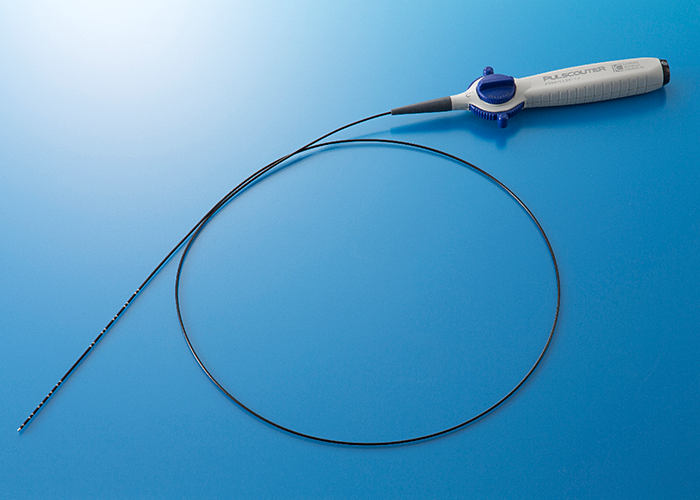

PULSCOUTER

Steerable & Bi-Directional Diagnostic Catheter

- 販売名

- カネカ電極カテーテル

- 医療機器承認番号

- 22900BZX00308000